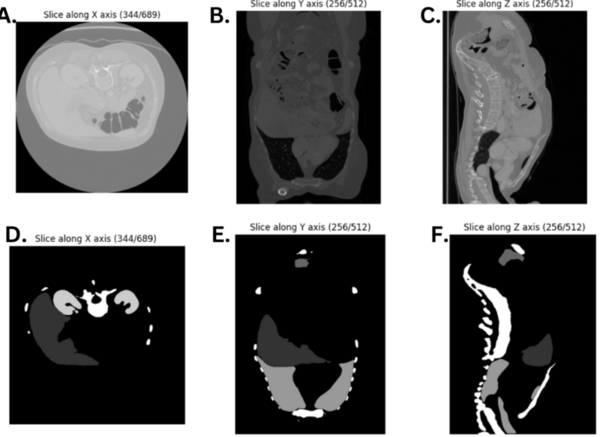

Read More...Unlocking robotic potential through modern organ segmentation

The authors looked at different models of semantic segmentation to determine which may be best used in the future for segmentation of CT scans to help diagnose certain conditions.